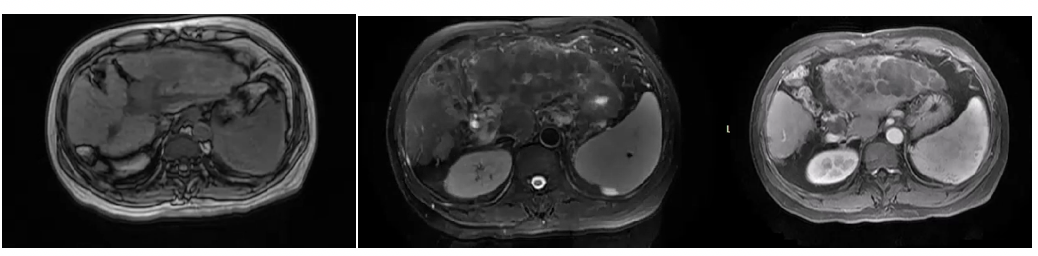

2021年7月27日MR提示,肝癌综合治疗后,病灶活动,大小约18.2cm×8.9cm,门静脉左支癌栓;肝门区淋巴结显示;肝硬化,腹水(图1)。

图1. 2021年7月27日MR